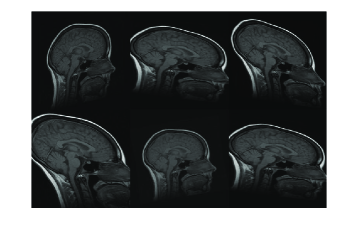

In Figure 7, three example registration results of randomly and affinely warped images are shown. The resulting images clearly show that registered source images are in good agreement with target images. Registration quality is measured over 30 randomly deformed images by mean of the square of the differences in intensity (MSE). Experiment has been done both in image scale and on standard scale to show improvement in MSE sense. Table-1 shows the MSE, maximum MSE and minimum MSE over 30 registration examples on image scale and on intensity scale respectively.